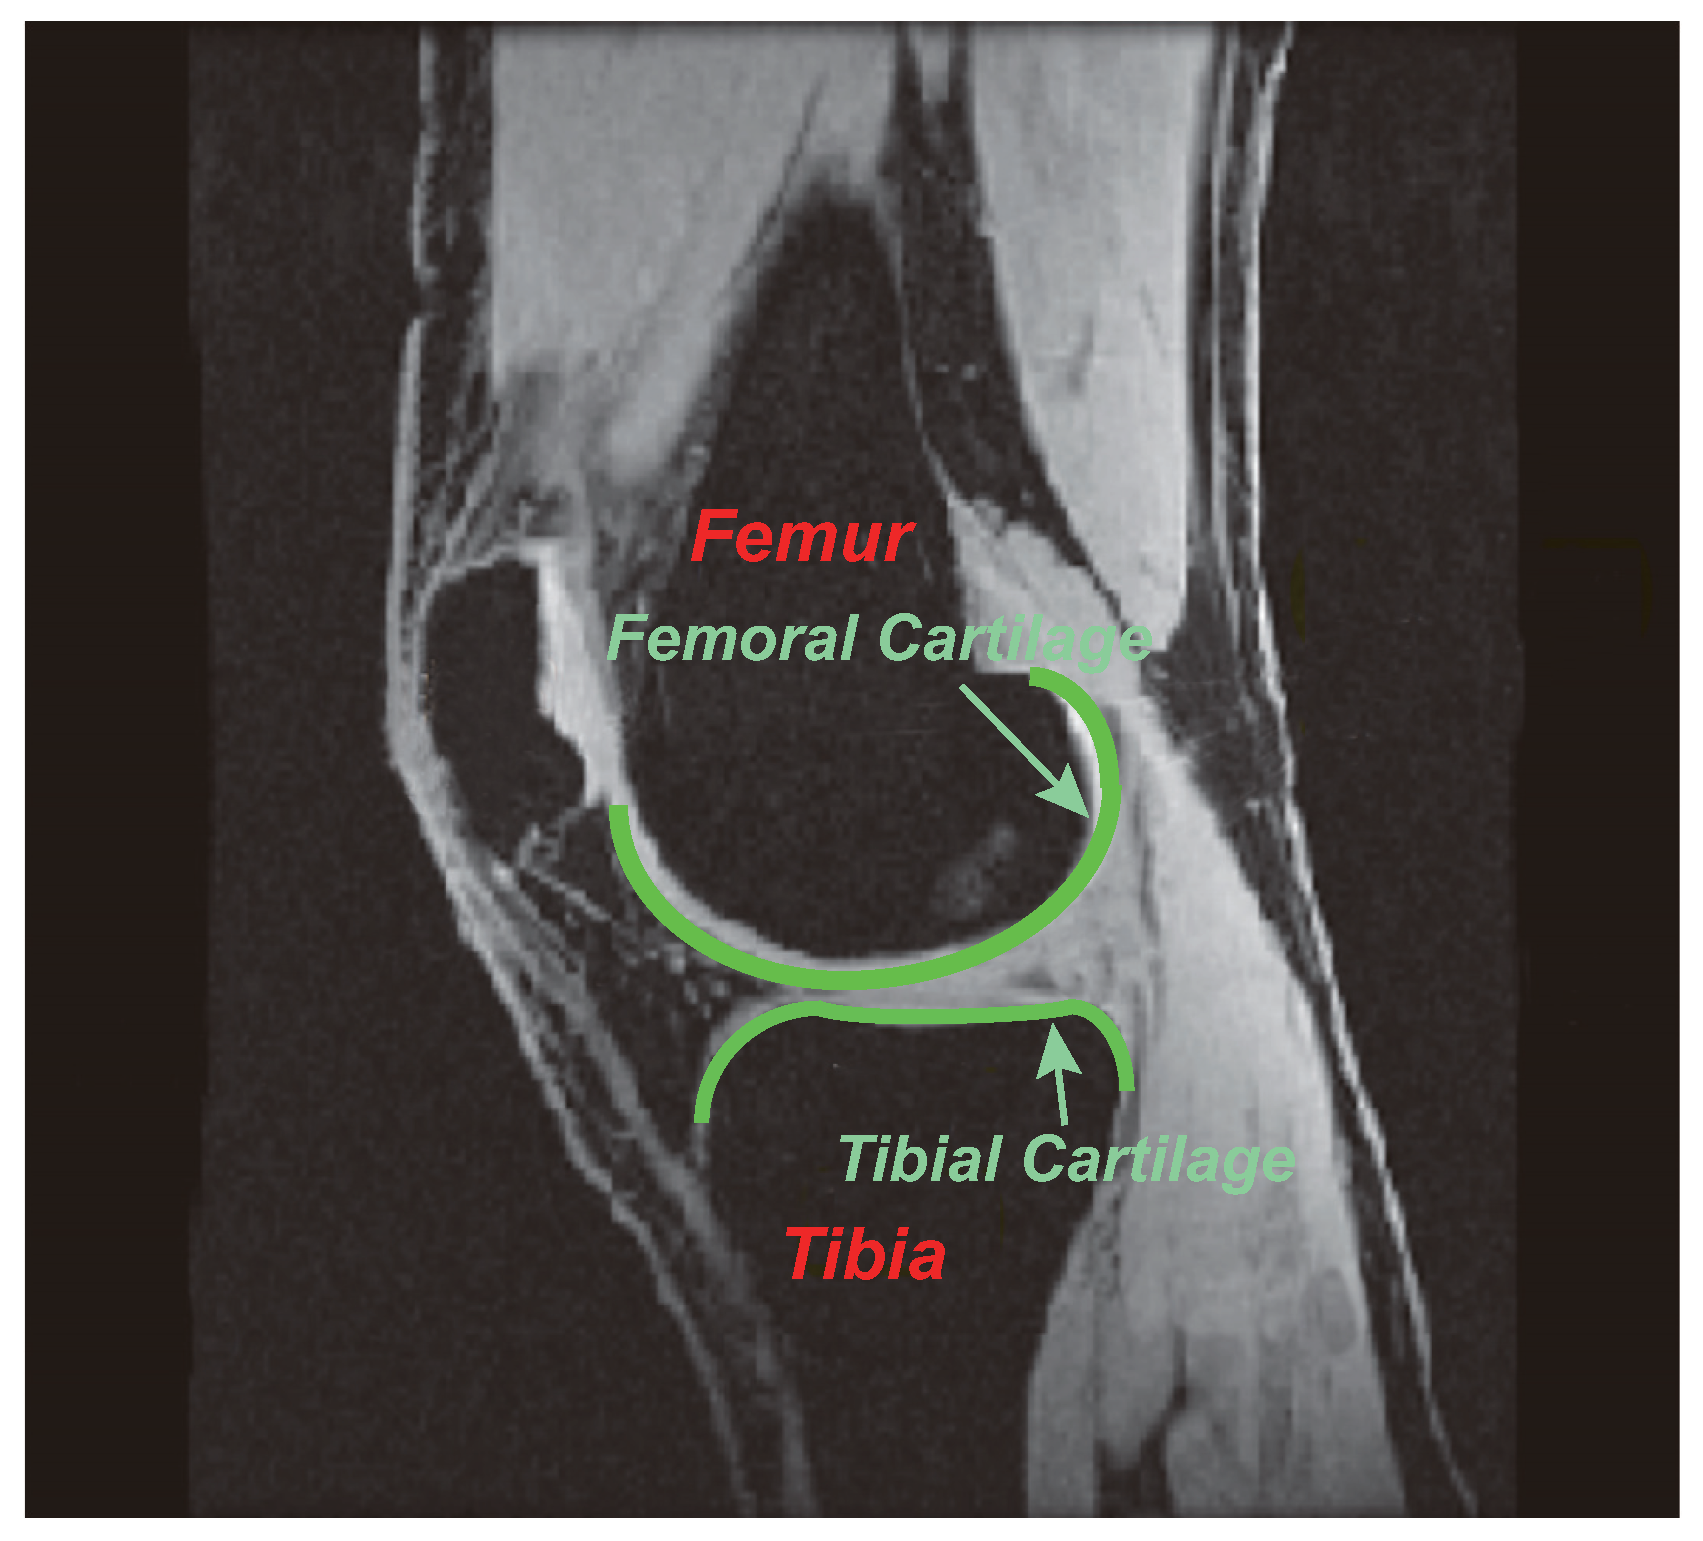

1. Introduction